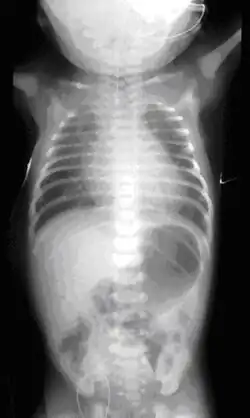

Etiologia nie jest poznana; uważa się, że jest ona wieloczynnikowa. Zwierzęce modele atrezji przełyku sugerowały nieprawidłową ekspresję genu Sonic hedgehog (Shh) jako jedną z przyczyn, ale jak dotąd nie potwierdzono roli ludzkiego homologu tego genu w patogenezie malformacji. Zidentyfikowano przynajmniej trzy zespoły wad wrodzonych o zbadanym podłożu genetycznym, w których obrazie klinicznym stwierdza się atrezję przełyku[2]. Zdecydowana większość przypadków OA jest jednak sporadyczna, a ryzyko wystąpienia wady w kolejnej ciąży wynosi około 1%. Możliwa jest diagnoza prenatalna wady na podstawie badania USG płodu, począwszy od 18. tygodnia ciąży. Prawdopodobieństwo wystąpienia atrezji przełyku u noworodka jest zwiększone w przypadku wielowodzia. Potwierdzenie rozpoznania stawiane jest na podstawie zdjęcia rentgenowskiego klatki piersiowej i brzucha dziecka. Leczenie wady jest chirurgiczne; rokowanie bezpośrednio zależy od masy urodzeniowej dziecka i od ewentualnej obecności towarzyszących wad serca. Przed wprowadzeniem chirurgicznych metod leczenia wada była letalna.

Najwcześniejszym objawem wady jest wielowodzie, wynikające z faktu, że płód nie połyka wód płodowych. USG może ujawnić obecność malformacji (uwidocznienie przepływu płynu w obu kierunkach w obrębie górnej, ślepo zakończonej „kieszeni” przełyku). W wariancie bez przetoki widoczny jest także niedostatek płynu w żołądku i dwunastnicy. Noworodek z całkowitą atrezją przełyku rodzi się z dusznością i sinicą, może wystąpić kaszel, czkawka i tachypnoe. Noworodek nie może przełykać śliny, której nadmiar wydostaje się przez nos. Po odśluzowaniu jamy nosowej i ustnej dziecka, objawy ustępują, by powrócić po krótkim czasie, co jest pierwszym sygnałem wady. Przy podejrzeniu niedrożności dziecka nie wolno karmić, zanim wada nie zostanie wykluczona. Gdy założenie zgłębnika 10-12 F jest niemożliwe z powodu oporu, istnienie wady jest niemal pewne. Standardowym działaniem po rozpoznaniu jest natychmiastowe założenie przez nos lub usta sondy Replogle’a służącej odsysaniu śliny i zapobiegającej jej aspiracji do dróg oddechowych przez dziecko. Przed zabiegiem chirurgicznym konieczne jest określenie typu malformacji[38].